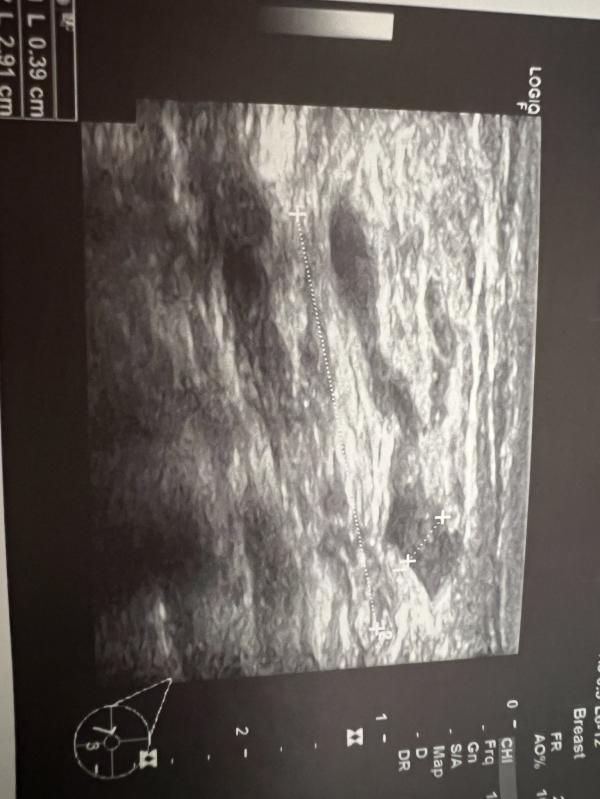

Дівчата в кого було розширення молочних проток? Була в мамолога, він подивився і сказав, що в грудях нічого не відчуває, ніяких змін

Але узі показує це